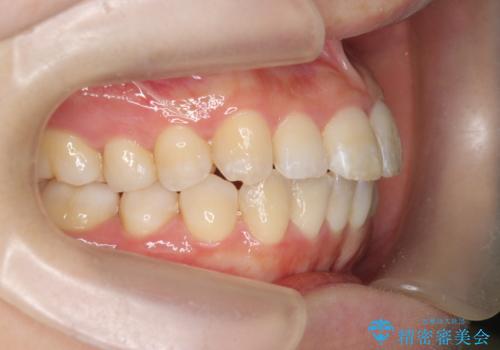

インビザラインで出っ歯の治療

- 「目立つ前歯の出っ歯をなんとかしてほしい。」と矯正治療を希望され来院されました。

突出した上顎の前歯に加え、ガタつきの目立つ下顎の歯列も同時にマウスピース矯正インビザラインで整えていきます。

突出間(所謂 出っ歯)のある前歯の位置は大幅に改善され、審美性が大きく向上しました。

加えて奥歯も噛み合わせも良くなったことで、咬合状態が安定しより安定した歯列を獲得することができました。